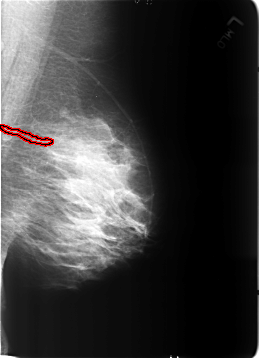

B_3212_1.LEFT_MLO

FILE: B_3212_1.LEFT_MLO.OVERLAY

TOTAL_ABNORMALITIES 1

ABNORMALITY 1

LESION_TYPE CALCIFICATION TYPE VASCULAR DISTRIBUTION N/A

ASSESSMENT 2

SUBTLETY 3

PATHOLOGY BENIGN_WITHOUT_CALLBACK

TOTAL_OUTLINES 1

BOUNDARY